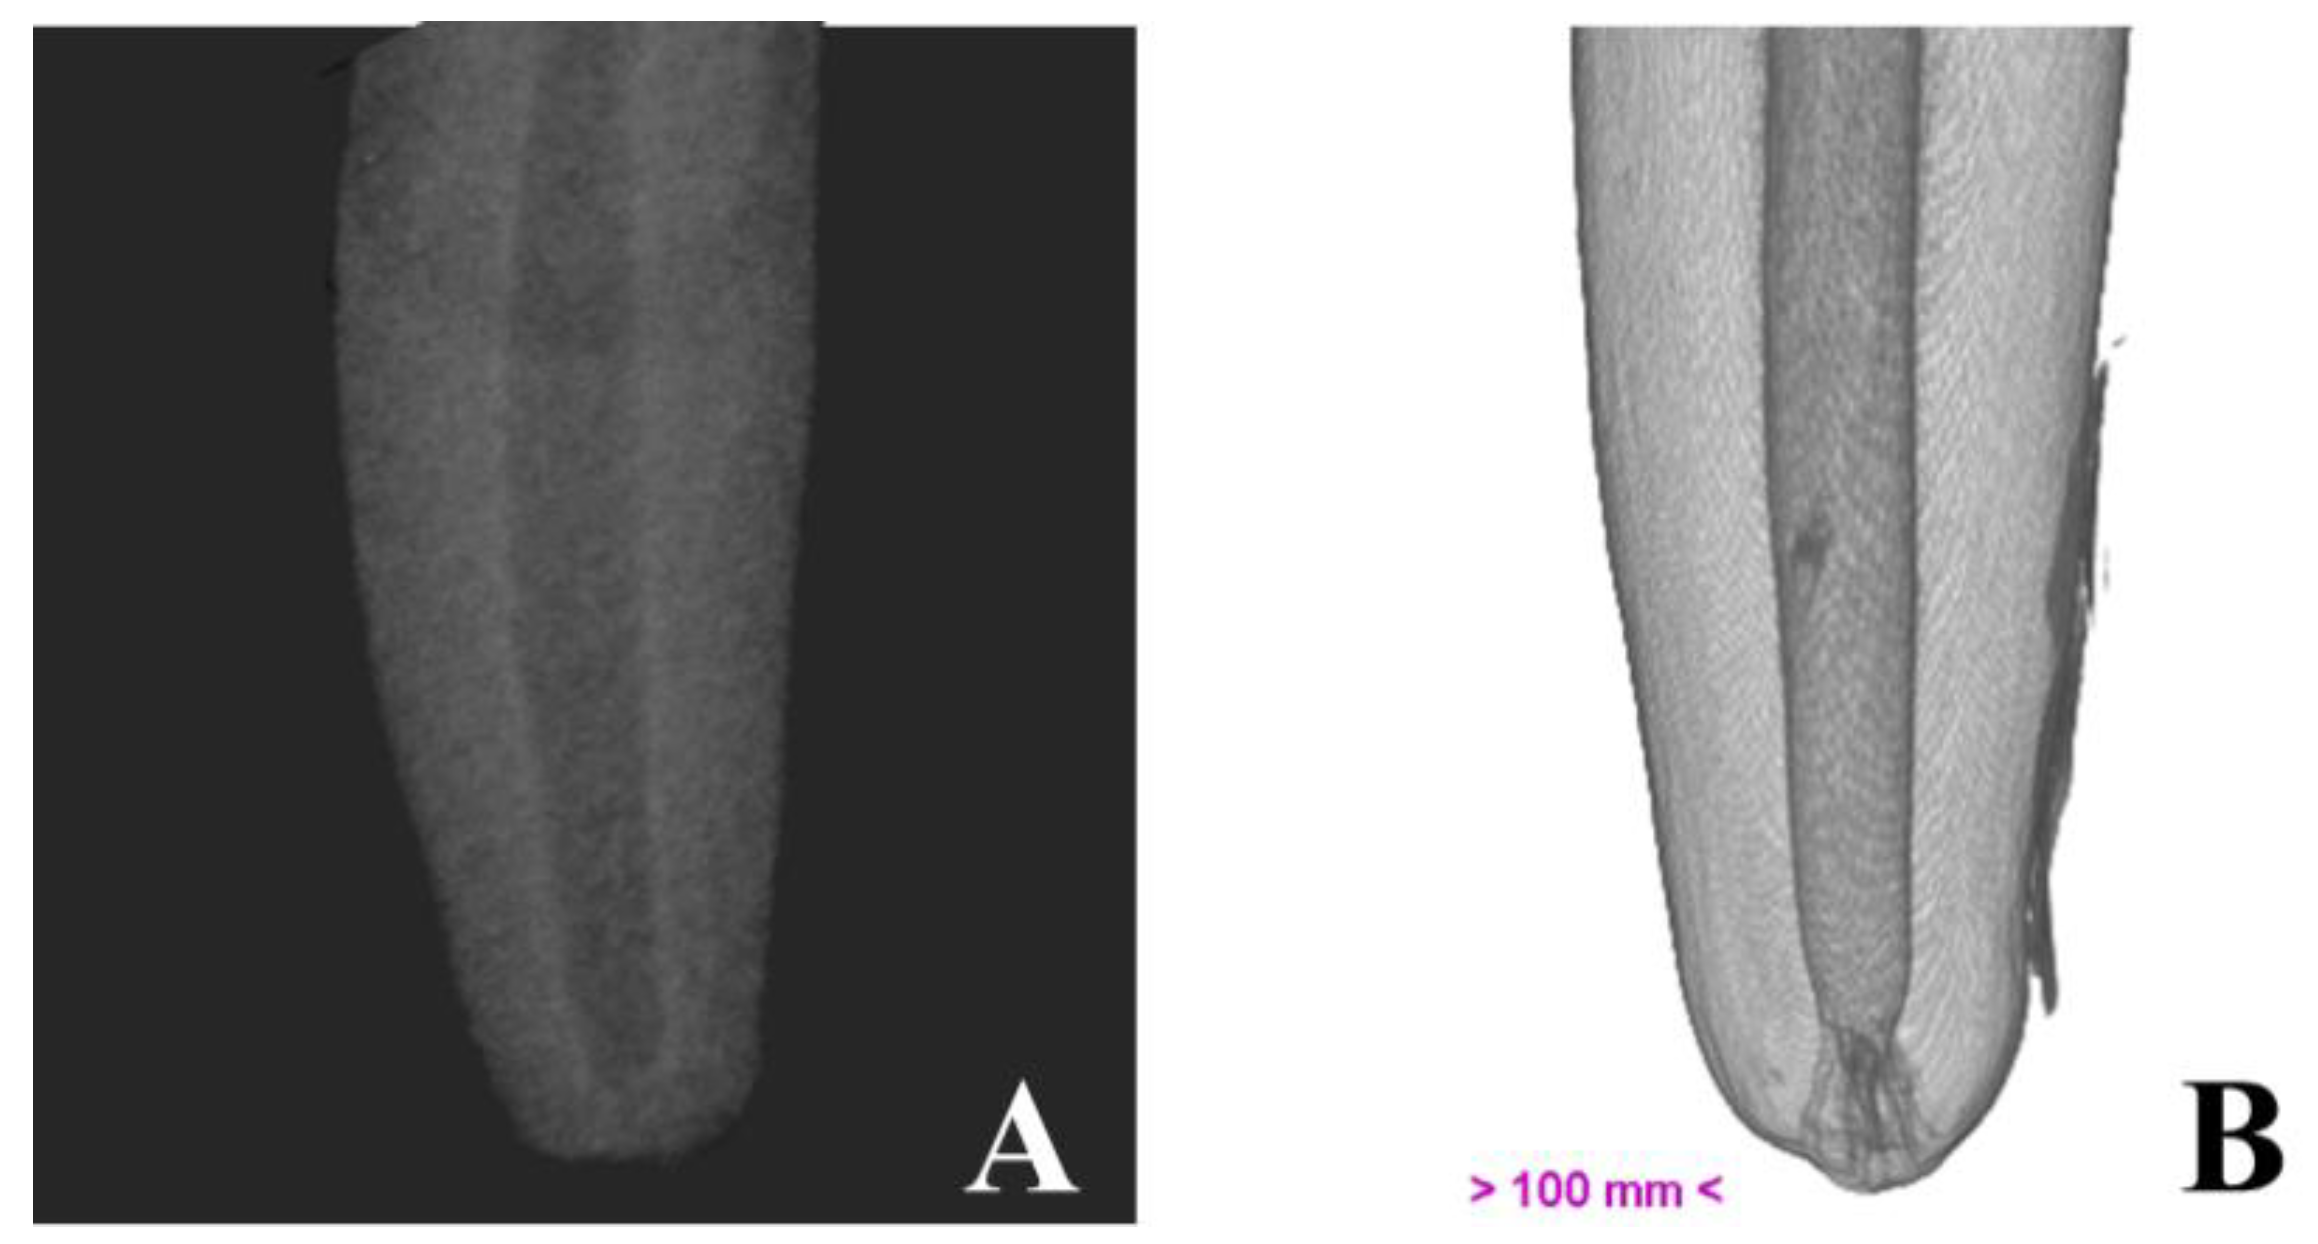

Micro-computed tomography allowed us to visualize dental structures which cannot be identified as effectively on dental radiography, with a rotation amplitude of 360° (Figure 3). The limits of the pulp canal can be observed in high detail. The apical delta at the bottom of the pulp canal, which is not visible on dental X-ray, is shown with great precision on mCT images (Figure 4).

Figure 4. Illustrative image of the canine root, obtained by dental radiography (A) and by micro-computed tomography (B).